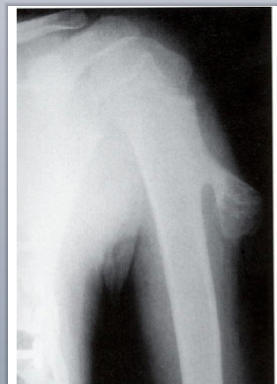

Ewing Sarcoma/PNET

Second most malignant bone tumor in kids

What is this?

Small round blue cells with neural phenotype and glycogen that stain with CD99; no bone/cartilage matrix